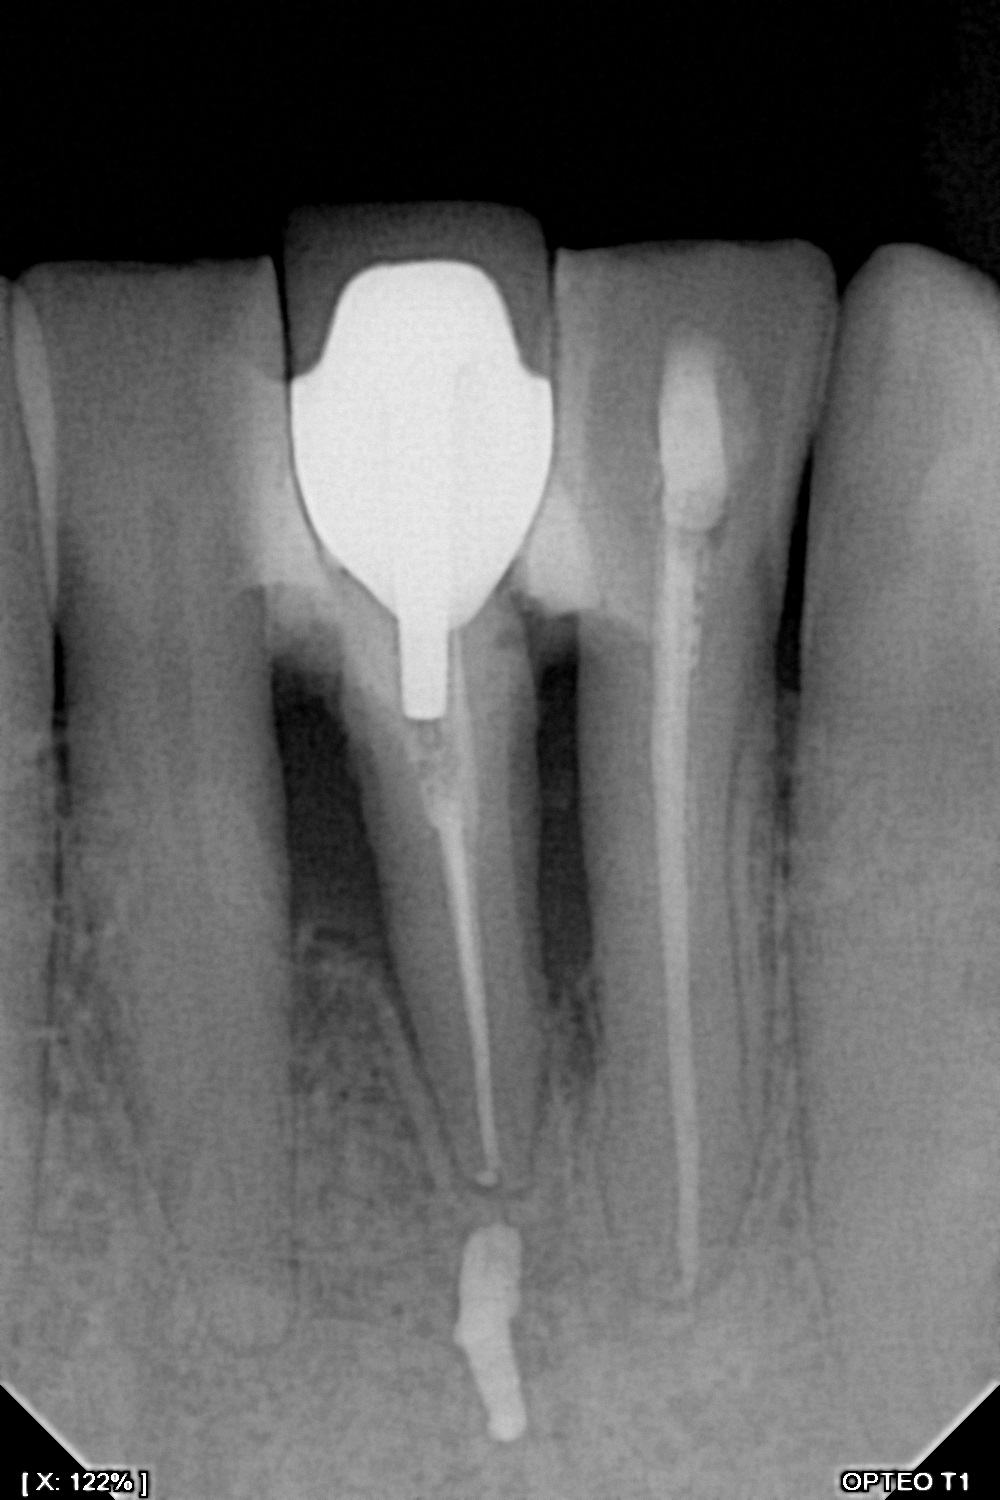

سنسور رادیوگرافی تک دندان مدل OPTEO

سنسور رادیوگرافی دیجیتال دندان مدل Opteo

سنسور ديجيتال راديوگرافي دندان مدل Opteo T1

سنسور پنج لایه و 14 بیتی با قدرت تفکیک بیش از 16000 رنگ در حد فاصل سیاه و سفید

Full HD sensor - CMOS sensor 26.3 lp/mm

Grey levels: 14 bits - 16384 grey levels

600mm² Sensitive surface Direct USB - without box